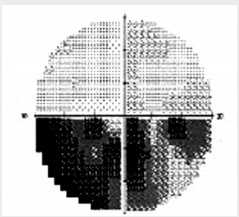

Выполнены общеклинические и офтальмологические исследования, статическая периметрия (см. рис. 3).